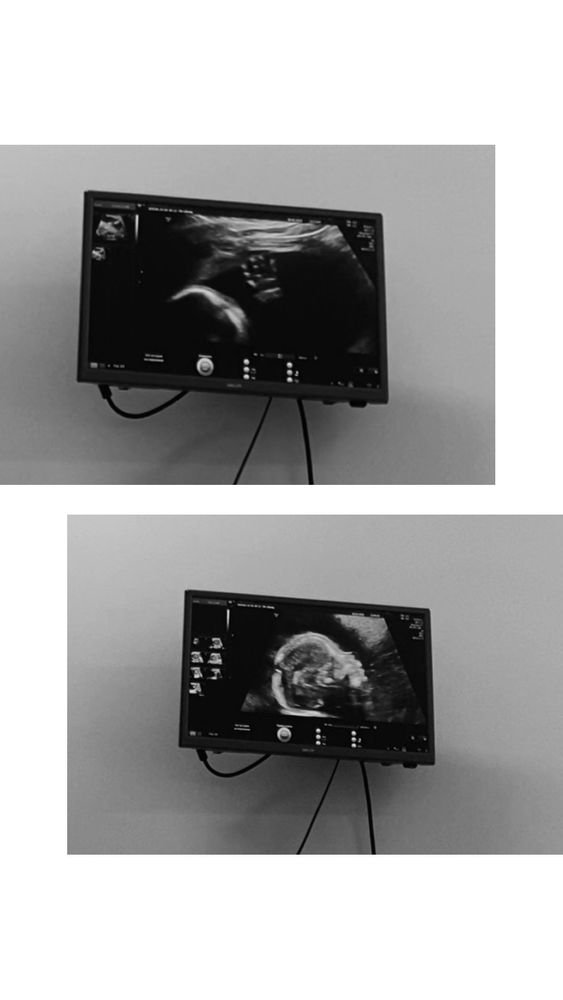

2 скрининг 🖤

Как же я переживала из-за первого скрининга. Напугали что у малыша высокий риск СД из того, что не увидели носик. По Нипту все отлично , на втором скрининге идеальные показатели. Спасибо сыночек что ты здоровый❤️ Я верила что с тобой все хорошо 🙏🏻